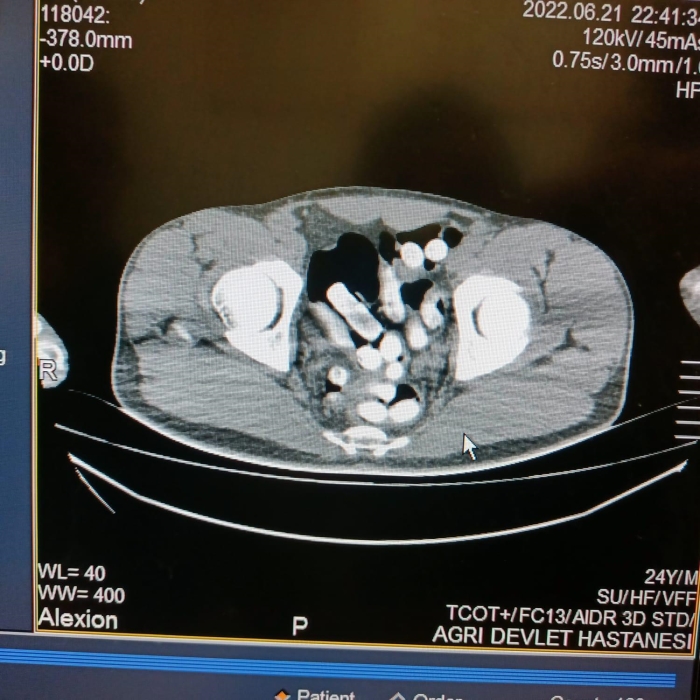

İl Emniyet Müdürlüğü Narkotik Suçlurla Mücadele Şube Müdürlüğü ekipleri, uygulama noktasında durdurulan otobüste yolculuk eden İranlı M.H.'nin üzerini aradı. Polisin midesindeki şişlikten şüphelendiği M.H., 6 kapsül halinde 62,35 gram afyon sakızını kustu. Hastaneye götürülen M.H.'nin çekilen röntgeninde mide ve bağırsak kısmında başka kapsüller bulunduğu da görüldü. Ek gözaltı süresi alınan şüpheli, doğal yollarla mide ve bağırsağındaki afyon sakızlarını çıkardı.

Midesinden 102 kapsül halinde 1 kilo 126 gram afyon sakızı çıkarılan şüpheli, sevk edildiği adliyede çıkarıldığı hakimlikçe tutuklandı.